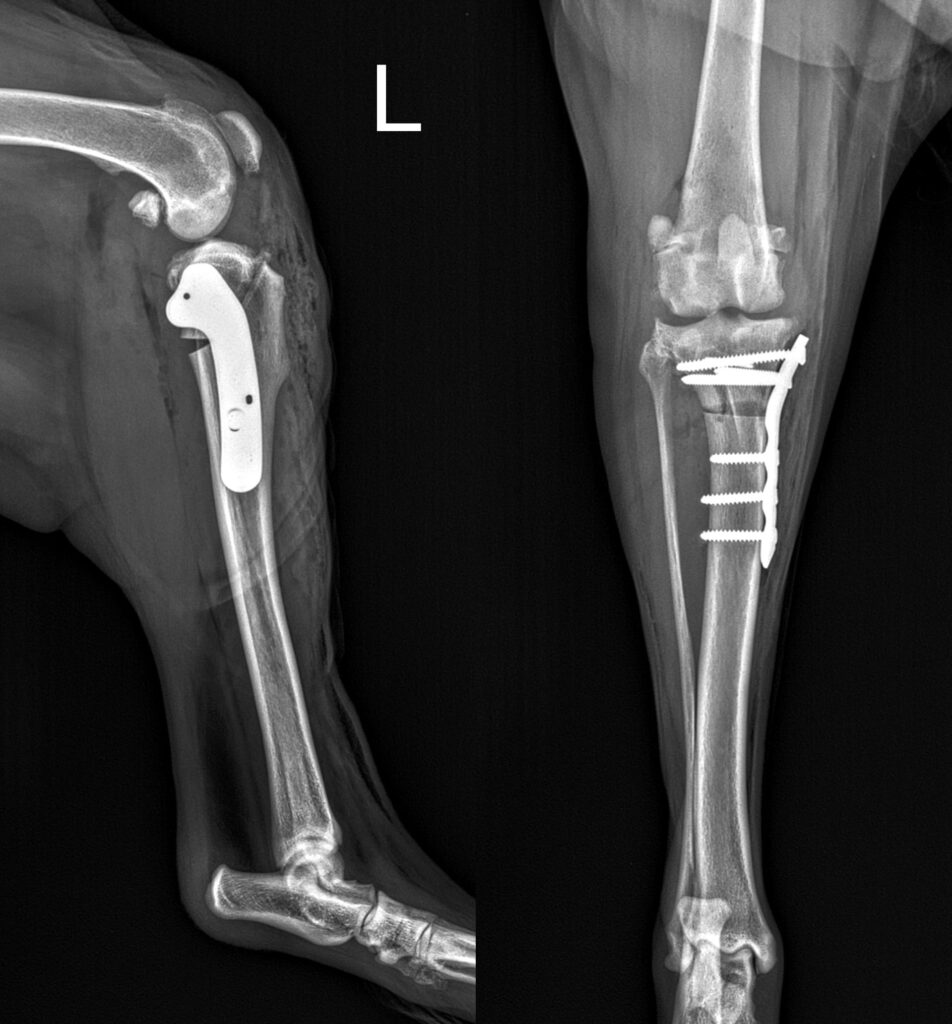

• Stabilisation ligamentaire du genou

Stabilisation ligamentaire